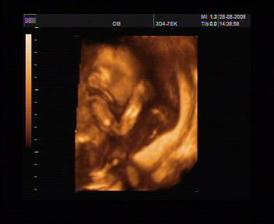

28.8. (20+3) 3D UTZ i s nastávajícím tatínkem, bylo to super, miminko předvádělo prostocviky a ukázalo nám, že rtíky i patro má v pořádku (maminčiny obavy kvůli rod. anamnéze). Hurá! 🙂)